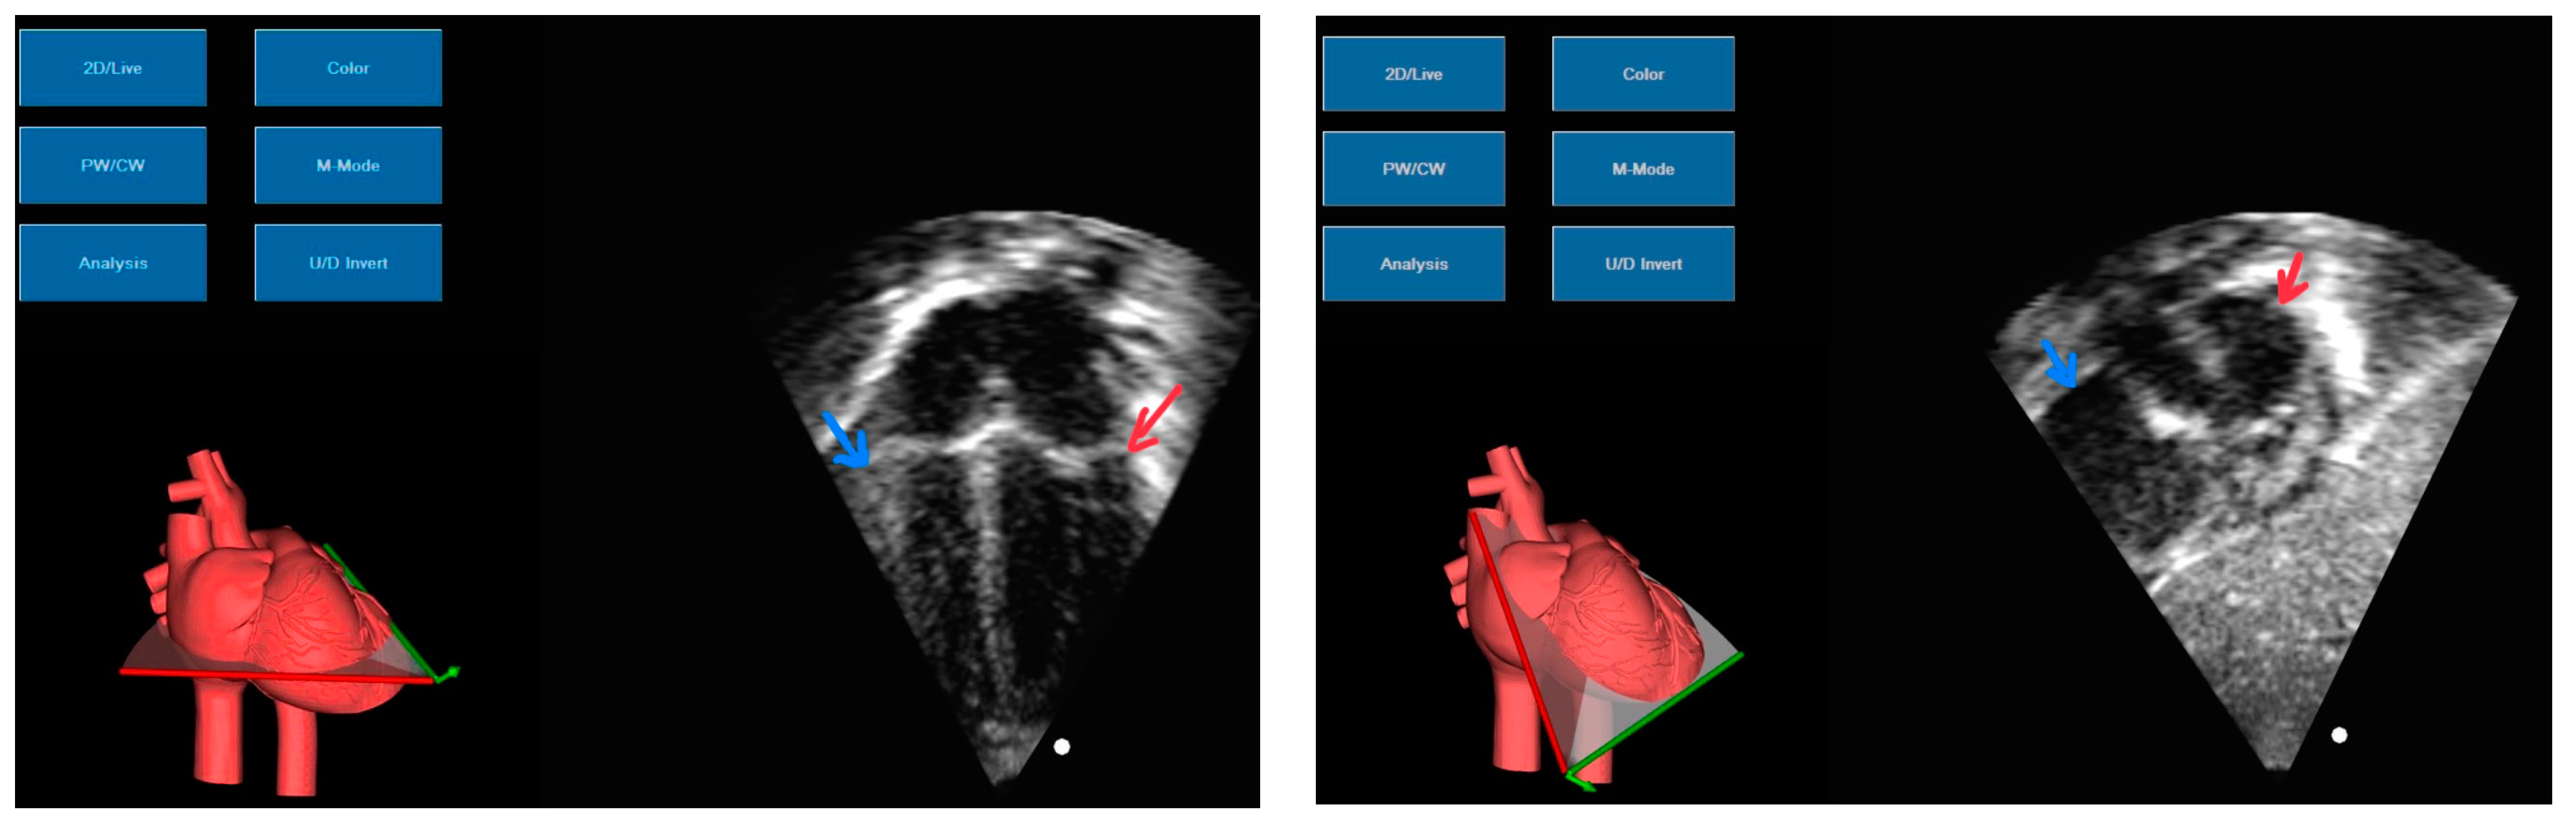

Pericardiocentesis: In our unit, pericardiocentesis is performed by the neonatologists at the patient’s bedside, with the help of US guidance, shortening the waiting time for intervention. We consider this to be one of the key factors in the management of PEff in our unit. To guide the pericardiocentesis, US images are obtained in an anatomical position, to facilitate the insertion of the needle parallel to the lateral wall of the right ventricle. Two views are acquired, an apical view and a subcostal view (Figure 5). In the apical view, the needle can be seen advancing from the apex, parallel to the right ventricle. We use a short cannula for access, followed by fluid removal, insertion of a guidewire, and finally, a short polyurethane catheter insertion inside the pericardium for draining a possible reaccumulation of the fluid. A simplification of the access procedure is shown in Figure 6.

Figure 5. Images obtained from the cardiac US simulator. On the left—apical view, on the right—subcostal view. Red arrow showing left cavities, blue arrow showing right cavities.